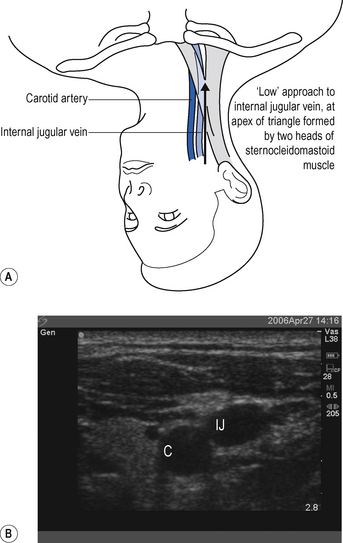

The internal jugular vein runs from the jugular foramen at the base of the skull (immediately behind the ear) to its termination behind the posterior border of the sternoclavicular joint, where it combines with the subclavian vein to become the brachiocephalic vein. Throughout its length it lies lateral, first to the internal and then common carotid arteries, within the carotid sheath, behind the sternomastoid muscle (Fig. 15.1A). Ultrasound demonstrates the close proximity of the vein to the carotid artery (Fig. 15.1B). Many approaches to the internal jugular vein have been described. A typical landmark approach is from the apex of the triangle formed by the two heads of the sternomastoid (Fig. 15.1).

Look for the internal jugular vein pulsation. If compressed, the internal jugular can usually be seen to empty and refill.

Look for the internal jugular vein pulsation. If compressed, the internal jugular can usually be seen to empty and refill. Introduce the needle from the apex of the triangle at an angle of 30° and aim towards the ipsilateral nipple.

It is a common mistake to assume the internal jugular vein is deep. Typically it is <2 cm from the skin. Do not introduce the needle to its full length. There is a danger of puncturing the apex of the lung.